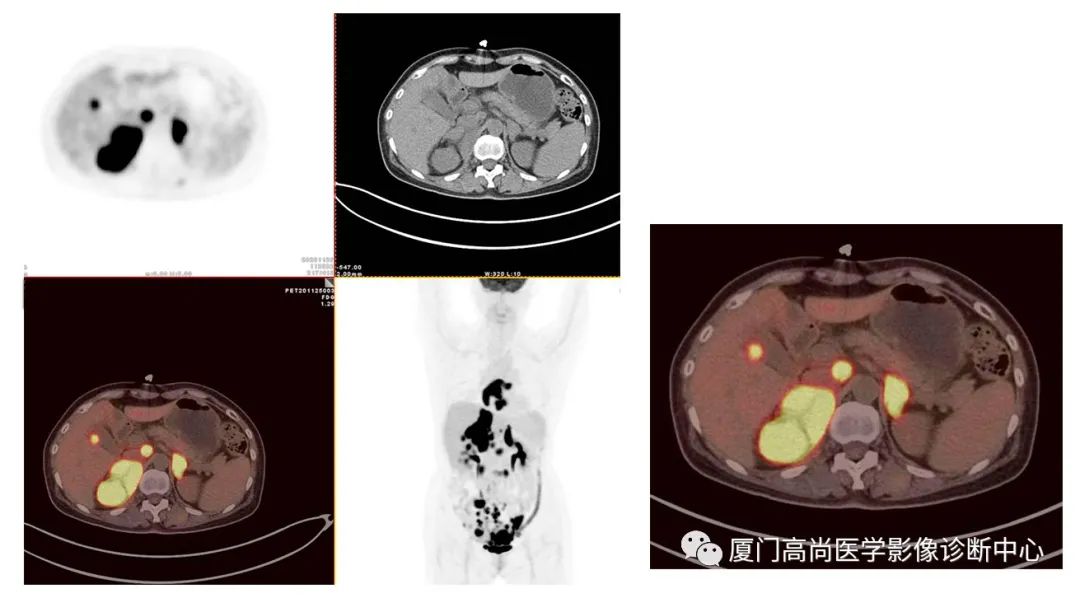

病例1:某男士,36歲,半年前摔傷,當(dāng)時無大礙,近幾個月來腰腿痛,并逐漸加重,消瘦10多斤。MRI檢查發(fā)現(xiàn)腰椎、骨盆 骨質(zhì)異常信號,查血各項腫瘤標(biāo)記物正常,因診斷不清而來做PET/CT檢查

淋巴瘤在骨骼、肝臟、脾臟、淋巴結(jié)表現(xiàn)

肝臟、脾臟、骨骼淋巴瘤病灶

骨骼、腋窩淋巴結(jié)病灶

PET/CT發(fā)現(xiàn) :全身多發(fā)淋巴結(jié)腫大,F(xiàn)DG攝取增高;肝臟、脾臟多發(fā)低密度結(jié)節(jié), FDG攝取增高;雙側(cè)扁桃體腫大,F(xiàn)DG攝取增高;全身多處骨骼破壞,F(xiàn)GD攝取增高;上述考慮為淋巴瘤

經(jīng)淋巴結(jié)穿刺活檢 :病理診斷為彌漫大B細胞淋巴瘤